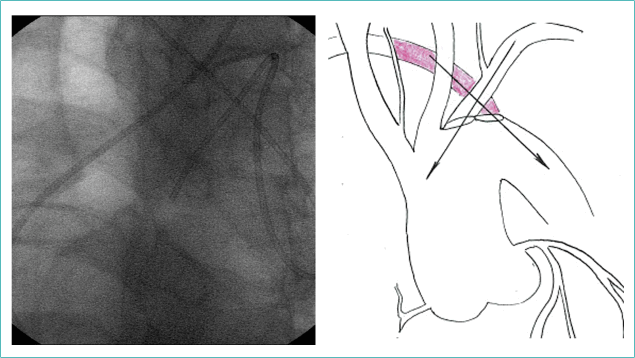

При наличии a. l. суть сложности заключается в пересечении путей катетеров из правой и левой подключичных артерий. При этом катетер из левой устремляется в восходящий отдел аорты, а из правой (из a. l.) соскальзывает в нисходящий отдел (рис. 5).

Рисунок 5. Ангиографическая и схематичная демонстрация пересечения путей катетеров из правой и левой подключичных артерий при наличии а. lusoria

Figure 5. Angiographic and schematic demonstration of the intersection of catheter pathways from the right and left subclavian arteries in the presence of a. lusoria

Для катетеризации ПКА была выбрана левая лучевая артерия. Модификации направляющих катетеров: JR, AR, EBU, AL оказались неподходящими, так как ни одним из них не удалось достичь необходимой поддержки — заведение коронарных проводников в зону окклюзии ПКА «выталкивало» катетер.